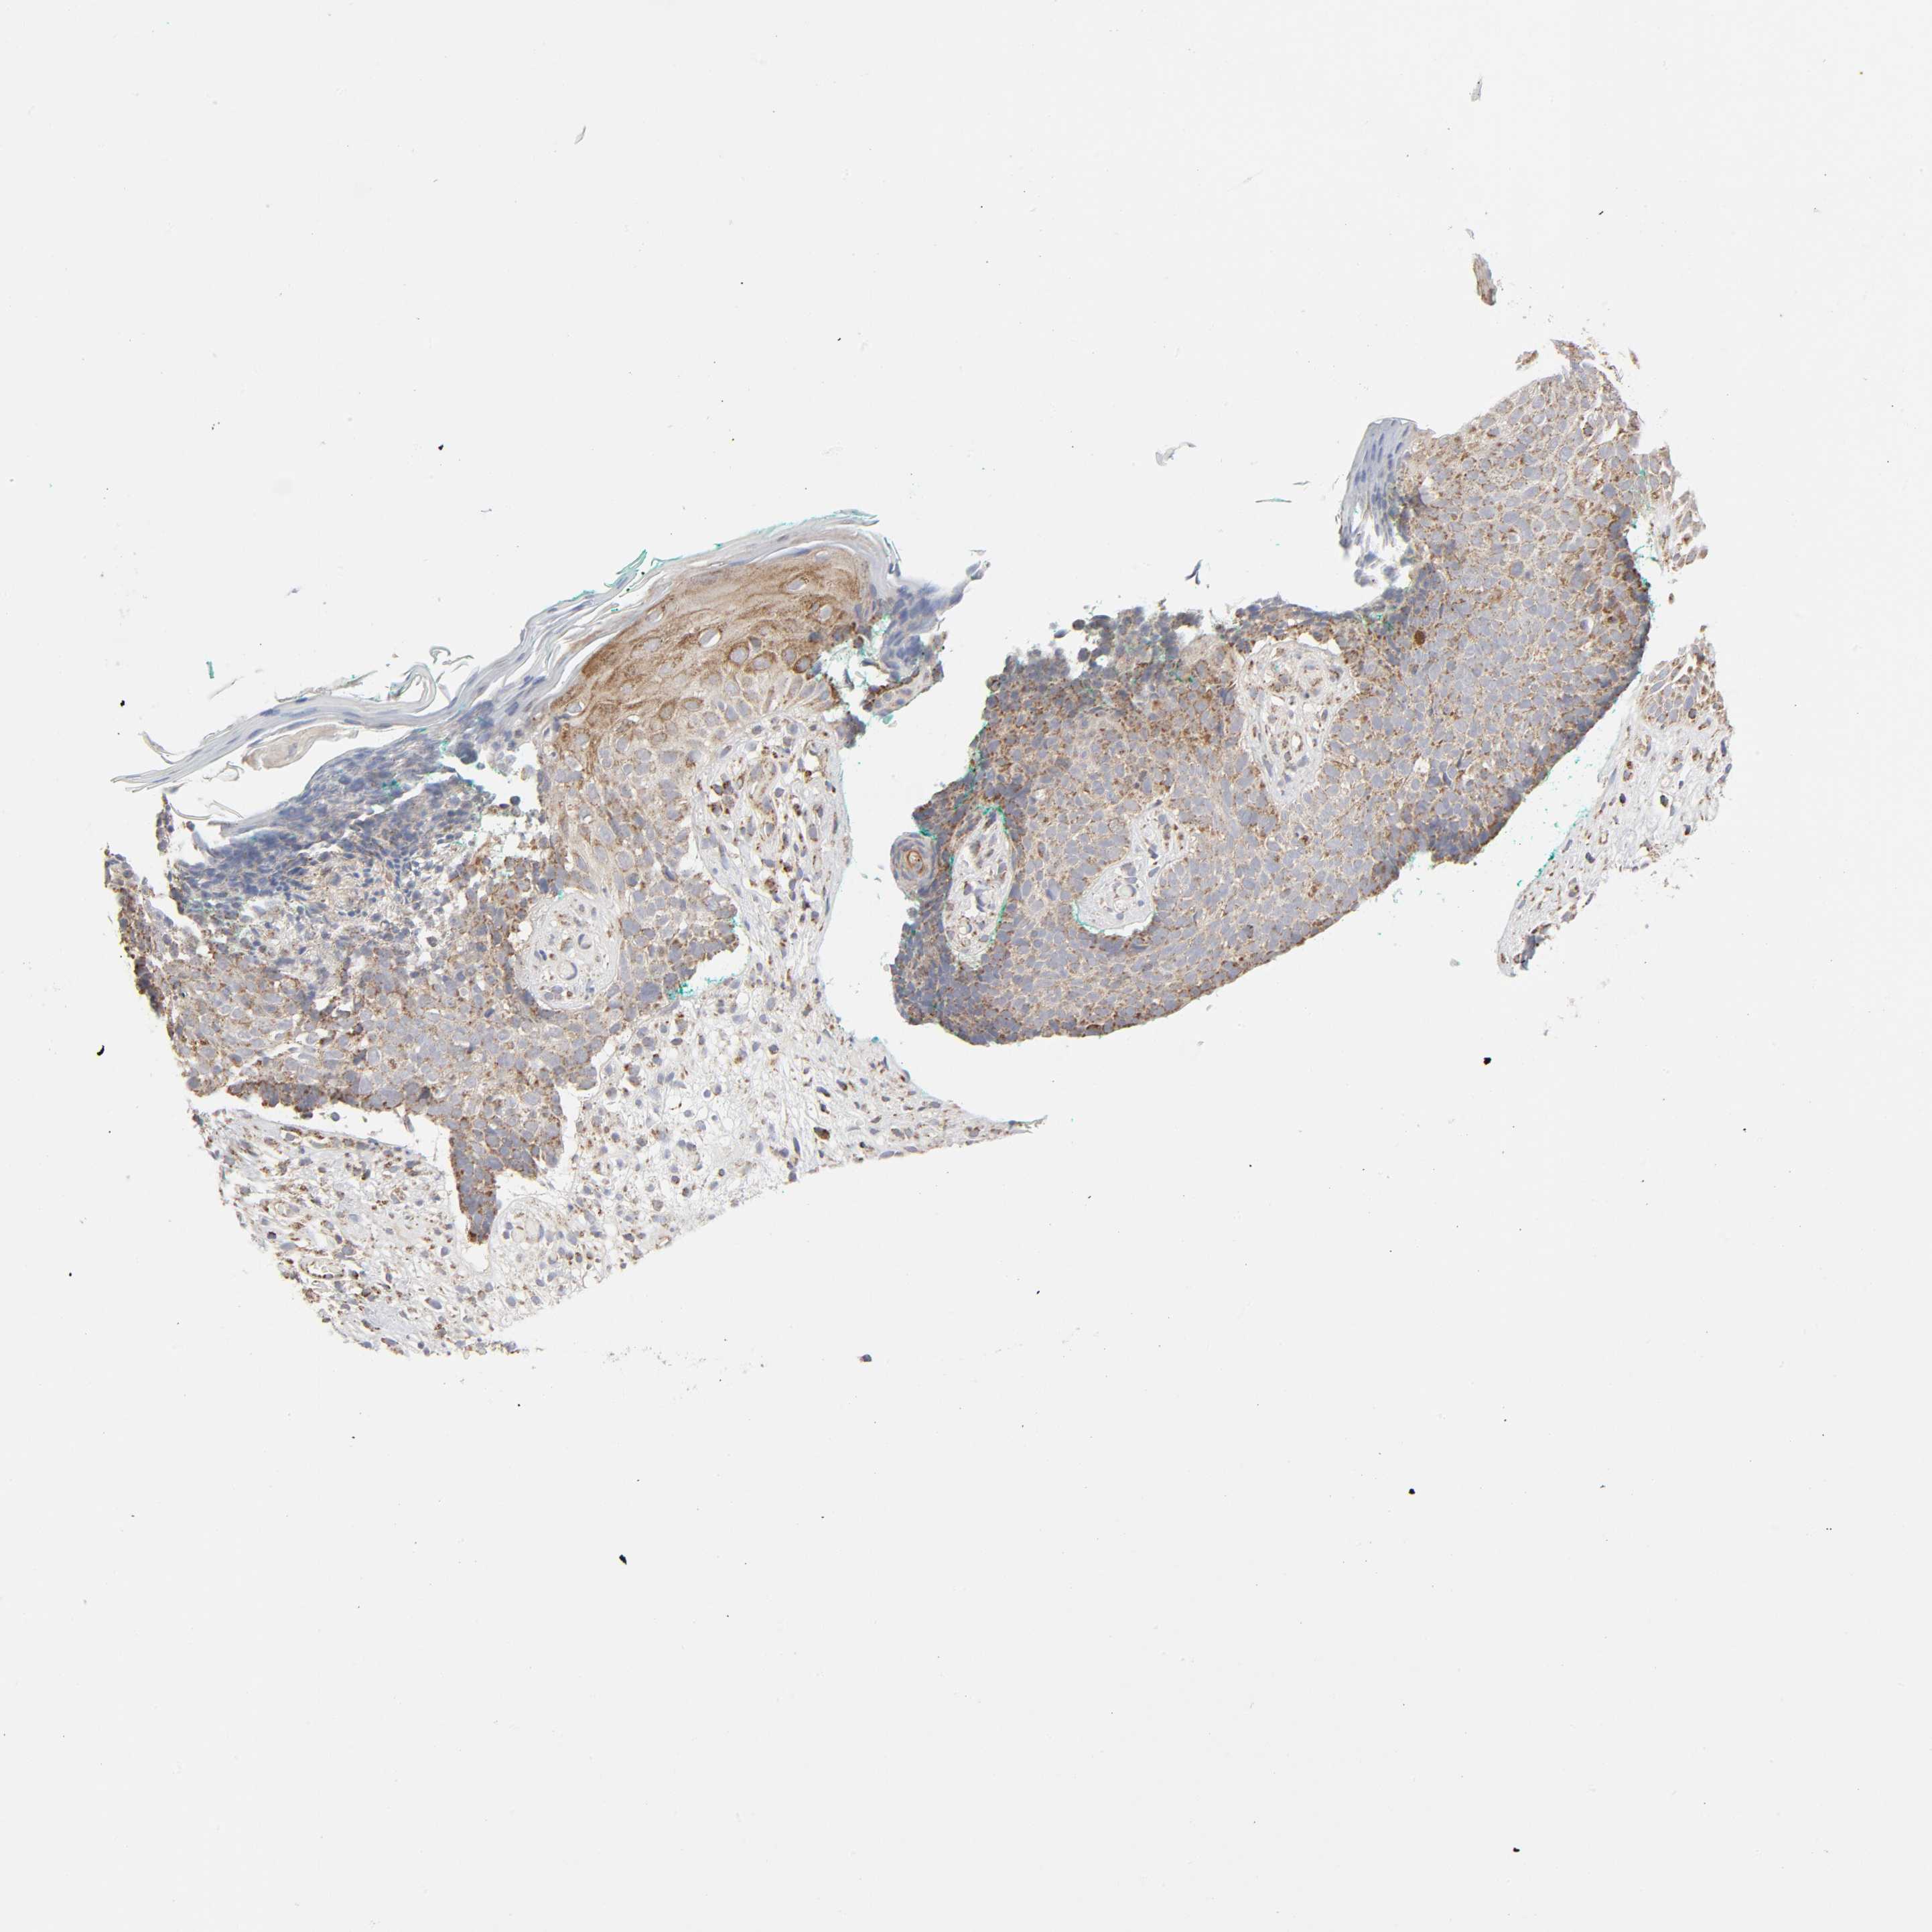

SKIN CANCER - Protein expressioni

A mouse-over function shows sample information and annotation data. Click on an image to view it in a full screen mode. Samples can be filtered based on level of antibody staining by selecting one or several of the following categories: high, medium, low and not detected. The assay and annotation is described here.

Antibody staining in the annotated cell types in the current human tissue is reported as not detected, low, medium, or high, based on conventional immunohistochemistry profiling in selected tissues. This score is based on the combination of the staining intensity and fraction of stained cells.

Each image is clickable and will lead to virtual microscopy that enables deeper exploration of all samples and also displays staining intensity scores, fraction scores and subcellular localization as well as patient and tissue information for each sample.

Antibody HPA004199

Squamous cell carcinoma, NOS